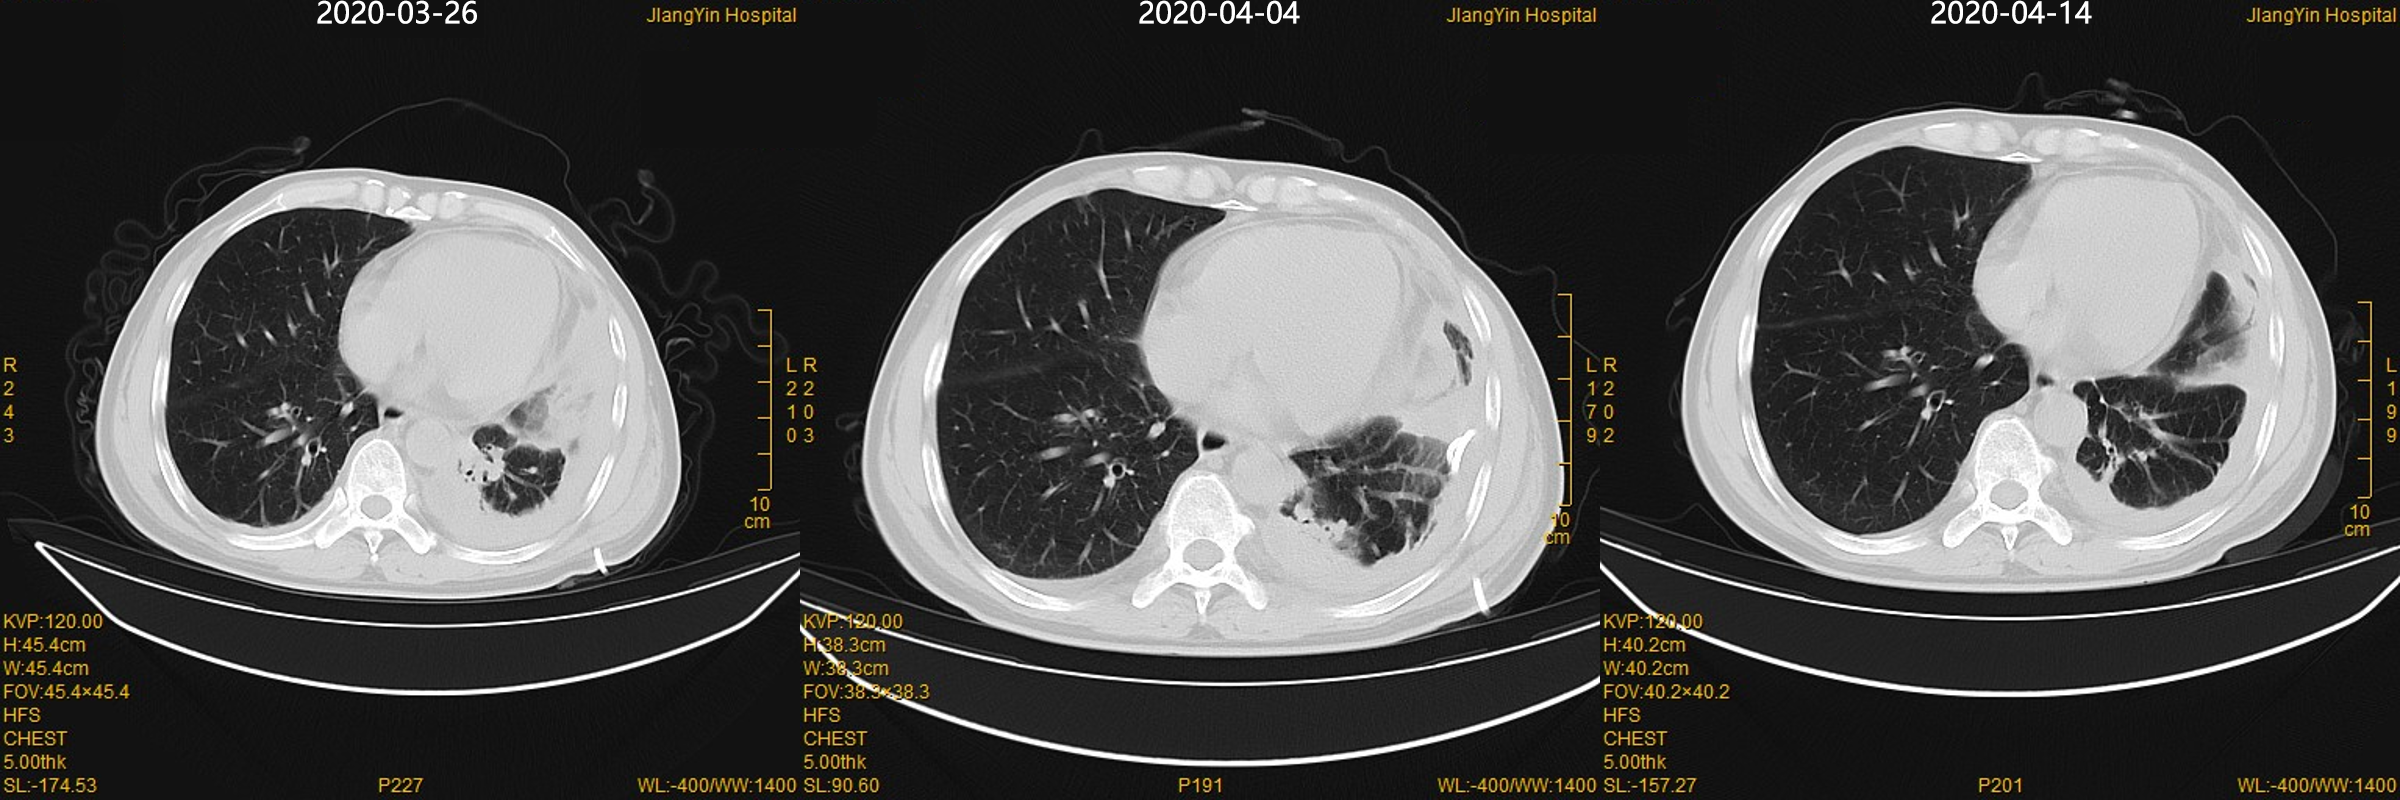

图4 住院期间胸部CT对比

(500mg,bid)抗感染治疗14d,同时尿激酶

10万u+生理盐水50ml胸腔冲洗。复查CT较前好转。